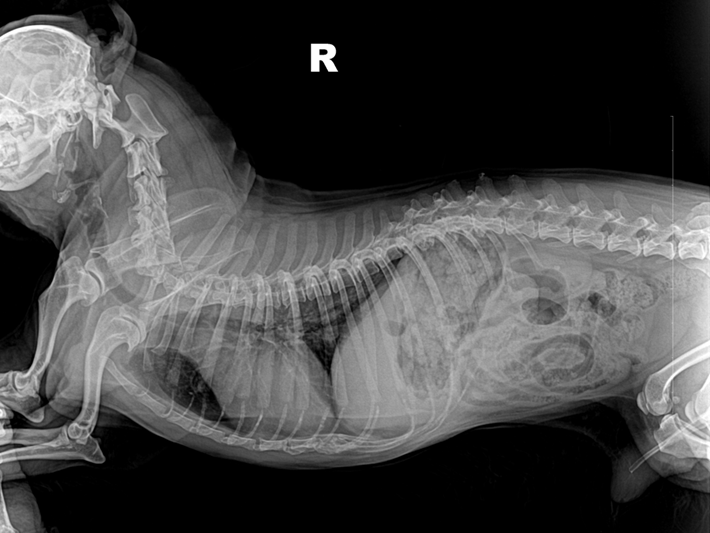

(2)识别X线影像中的颈椎、胸椎、腰椎和荐椎,并能确定属于位置(图6-12、图6-13)。

(3)识别椎间隙、椎间孔、棘突、横突的X线影像(图6-12、6-13)。

犬、猫正常脊柱由7节颈椎、13节胸椎、7节腰椎、3节荐椎和数量不定的尾椎连接而成。各椎骨间有椎间盘,但第1~2颈椎关节、3节荐椎之间无椎间盘。椎间盘由髓核和纤维环组成,呈软组织阴影,在X线片上表现为低密度的裂隙。邻近的椎间隙大致相等,但正常的第10~11腰椎椎间隙较狭窄。

犬椎体侧位投照显示似方形,多数脊椎可显示椎弓、椎管的背侧缘与腹侧缘、椎体前后端骨骺、棘突、横突和椎体。猫的椎体较长,侧位显示似长方形,椎弓根、关节突欠清楚,椎间孔背侧缘不如犬易见。棘突在腹背位投照时呈致密狭长的断面高密度阴影。侧位投照时,相连椎骨的大小、形状和密度大致相同。第2颈椎棘突靠近第1颈椎椎弓,或与之重叠。第6颈椎横突宽大,呈翼状。胸椎椎体长度略比颈椎椎体短。第11胸椎棘突垂直向上,称为直椎。直椎之前的胸椎棘突斜向后上方,而直椎以后的胸腰椎棘突则斜向前上方。后段4~5节胸椎的的关节后突下方、椎间孔的前上界处,可显示一细小、类三角形的副突阴影。